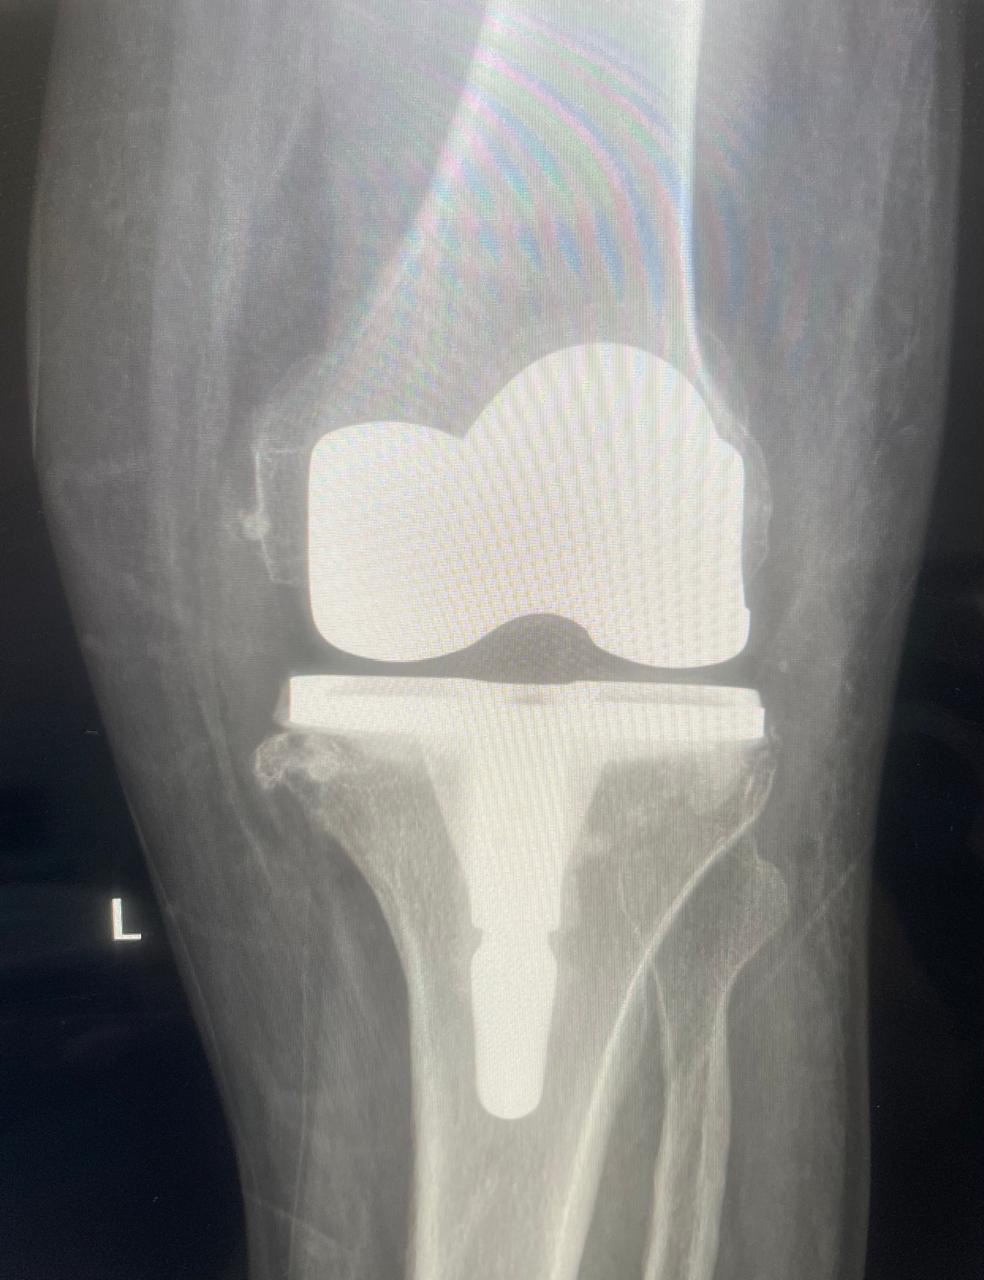

أعلن مستشفى القطيف المركزي إطلاق وحدة تخصصية لتبديل وترميم المفاصل، متوجاً انطلاقتها بإجراء 30 عملية جراحية ناجحة للركبة، لتعزيز كفاءة الرعاية الطبية وتطوير الخدمات وفق أحدث المعايير العالمية المعتمدة.

وأوضح المستشفى التابع لتجمع الشرقية الصحي، أن الوحدة الجديدة انضمت رسمياً للوحدات التخصصية بقسم العظام، مبيناً أن نجاح العمليات الثلاثين يعكس جاهزية الكوادر الطبية وتوفر التقنيات المتقدمة.

وبيّنت الجهات الطبية أن الوحدة تقدم منظومة رعاية متكاملة، تبدأ بتقييم وتشخيص دقيق لحالات تآكل المفاصل والإصابات المزمنة، وصولاً للتدخلات الجراحية المبتكرة.

وأضافت أن خطة العلاج تكتمل بتقديم برامج تأهيل وعلاج طبيعي متخصصة، تستهدف تسريع وتيرة تعافي المرضى بشكل آمن، وتحسين جودة حياتهم اليومية.